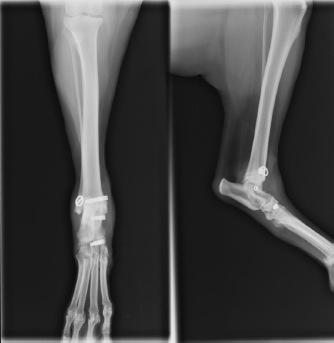

The surgical site was then closed plane by plane. Immediate postoperative radiographs showed a good implantation of the interference screws in the bone drillings through the distal tibia and the talus. However, the bone drilling corresponding to the distal insertion of the long head of the MCTL was not satisfactory: it was drilled between the tarsal midbone and tarsal bones II and III, while it should have been drilled through the tarsal midbone (Fig. 6).

An approximation in the third drilling (distal reconstruction of the long head of the MCTL) was observed during the immediate postoperative radiographic control (Fig. 6). No other intraoperative complications occurred. Unfortunately, postoperative advice was not followed properly. The bivalve resin boot was completely removed at only 2 weeks postoperatively. However, a first radiographic check at 11 weeks showed good valgus stability of the tibiotarsal joint and the orthopedic examination showed a return to subnormal function of the pelvic limb during locomotion. At 12 months postoperatively, valgus stability of the tibiotarsal joint was maintained and the pelvic limb returned to normal function during locomotion. At 16 months post-op, radiographic control showed ovalization of the bone tunnels with no clinical impact on the stability of the tibiotarsal joint (Fig. 7).

Avulsion of the long head of the left MCTL was diagnosed in a five-year-old overweight castrated male Australian Shepherd. The context was favorable to the implementation of the surgical ligament reconstruction technique previously described. Although the immediate postoperative radiographic control showed an approximation of the third drilling (distal reconstruction of the long head of the MCTL), the surgeon chose not to reopen the surgical site (Fig. 6). The reason for this choice was that sufficient tightening torque was perceived by the veterinary surgeon during the implantation of the 4x13-mm interference screw, which was compatible with satisfactory primary fixation of the UHMWPE implant according to his empirical experience. Although external restraint was maintained for only 2 weeks and the animal did not lose weight as advised, no postoperative complications were identified and one year after surgery, the animal regained normal locomotion. This synthetic MCTL reconstruction technique thus allowed a complete and durable functional and clinical recovery without the need for invasive transarticular immobilization, such as the placement of a transarticular external fixator (TEF). However, the use of a bivalve resin boot was recommended for a minimum of 6 weeks, which was not respected. In addition, the animal did not lose weight as advised. Early weight-bearing on the limb without any other form of restraint and the excess weight were potentially the cause of the progressive ovalization of the tunnels observed on the radiographic images taken 16 months postoperatively. In humans, obesity has been shown to be a leading risk factor for intraoperative complications in total hip arthroplasty (Haynes et al., 2017). Similarly, weight loss in dogs would be an essential element in the treatment of osteoarthritis, which is a frequent complication in osteoarticular surgery (Marshall et al., 2009). The ovalization of the tunnels could lead to a loss of biomechanical strength of the fixation system owing to a reduced contact surface in the bone tunnels at the bone/UHMWPE implant/interference screw interface. This loss of strength could even lead to implant slippage at this interface, resulting in a complete loss of functionality of the fixation system. However, none of this was observed from a clinical point of view during the 16 months of postoperative follow-up. The tibiotarsal joint always remained stable in valgus position. A secondary biological stabilization (Kulendra et al., 2011) may have reinforced or even supplemented the primary mechanical stabilization achieved during surgery and thus ensured durable stability of the tibiotarsal joint.

Fig. 6. Radiographic views of dog’s left pelvic limb from side (left) and front (right) in immediate postoperative period.